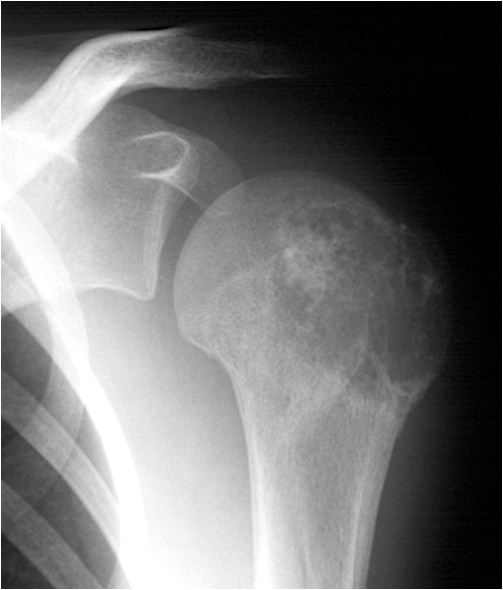

Fig. 19. Chondrobastoma: An expansile lesion involving theepiphysis, physis and metaphysis of the humerus is depicted. The lucent lesion shows cortex destruction and spotty matrix calcifications.